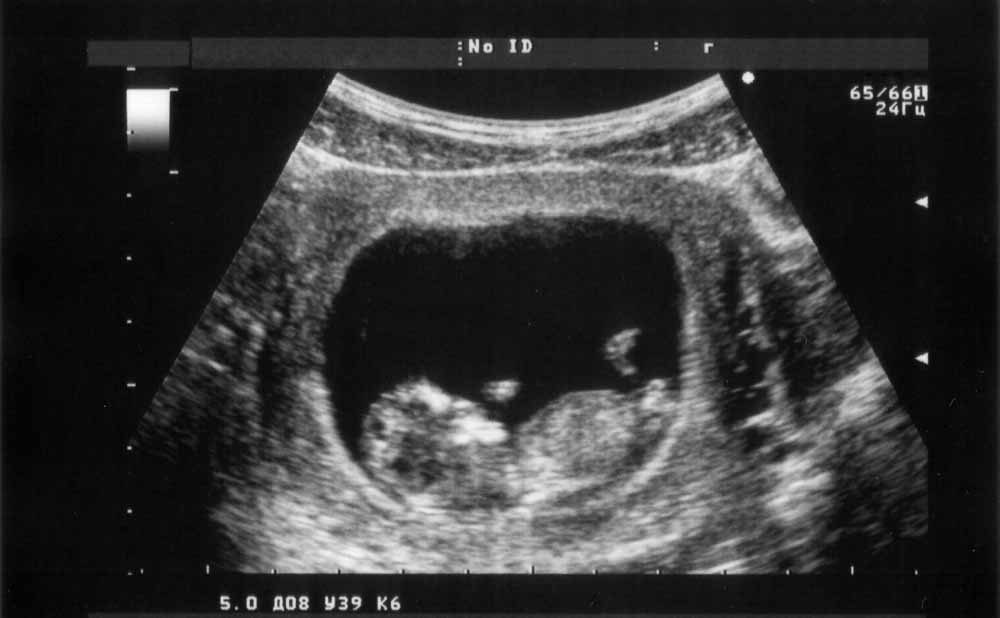

يعتبر الفحص بالموجات فوق الصوتية أو ما يعرف أيضًا بالسونار الطريقة الأضمن من أجل تحديد نوع الجنين! تخضعين عادةً لهذا الفحص ما بين الأسبوع الـ18 والـ22 من الحمل بهدف معرفة إذا كان الجنين يعاني من أي مشاكل أو تشوهات وليس فقط من أجل تحديد نوعه.

تعتمد مدى دقة هذا الفحص على عوامل عدة ومن بينها عمر الجنين ووضعيته. لكن عليك أن تنتبهي من أمر معين وهو التالي: يستنتج بعض الأطباء تلقائيًا أنك حامل ببنت في حال لم يتمكن من العثور على عضو الجنين الذكري إلا أن هذه الطريقة خاطئة.

لا يمكن للطبيب أن يؤكد في حال كنت حامل ببنت من خلال اعتماده على هذا العامل وحده إذ يجب أن يتمكن من رؤية أعضاء البنت التناسلية والبظر.

في هذا السياق، لا ننصحك بالخضوع للفحوصات قبل الأسبوع الـ18 من الحمل إذ لا تكون النتيجة مضمونة ولا يتمكن الطبيب من التفرقة بين الأعضاء التناسلية بسهولة.